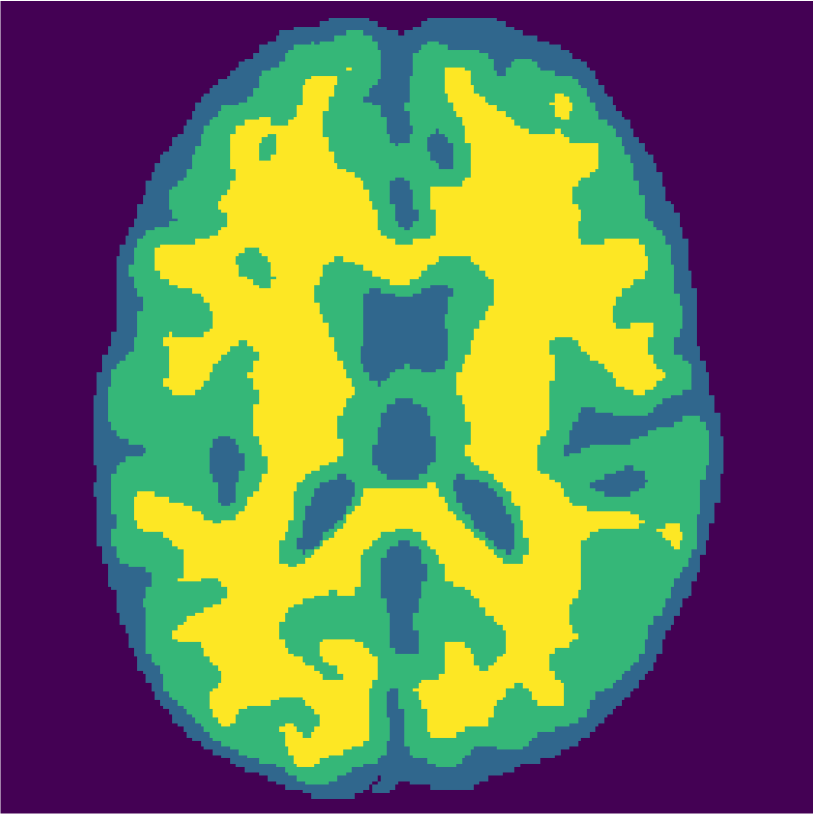

Examples of the segmentation results on one of the target test images are shown in Figure 8 for experiment 2.1, Figure 9 for experiment 2.2, and Figure 10 for experiment 2.3. Examples are shown after using 1 target patch per tissue for training, and after using 100 target patches per tissue for training. The results show that only the mrai-net classifier is able to predict a segmentation that approaches the ground truth with only 1 target patch per tissue for training (error for experiment 2.1 = 0.269, experiment 2.2 = 0.403, experiment 2.3 = 0.320), while the source and target classifiers cannot (source error for experiment 2.1 = 0.667, experiment 2.2 = 0.653, experiment 2.3 = 0.435; target error for experiment 2.1: 0.591, experiment 2.2: 0.614, experiment 2.3 = 0.596). After using 100 patches the source and target classifiers can predict a gross segmentation of WM, GM and CSF (source error for experiment 2.1 = 0.213, experiment 2.2 = 0.384, experiment 2.3 = 0.363; target error for experiment 2.1: 0.205, experiment 2.2: 0.368, experiment 2.3 = 0.368), but the mrai-net classifier prediction shows more details and a lower tissue classification error (error for experiment 2.1 = 0.111, experiment 2.2 = 0.276, experiment 2.3 = 0.284).